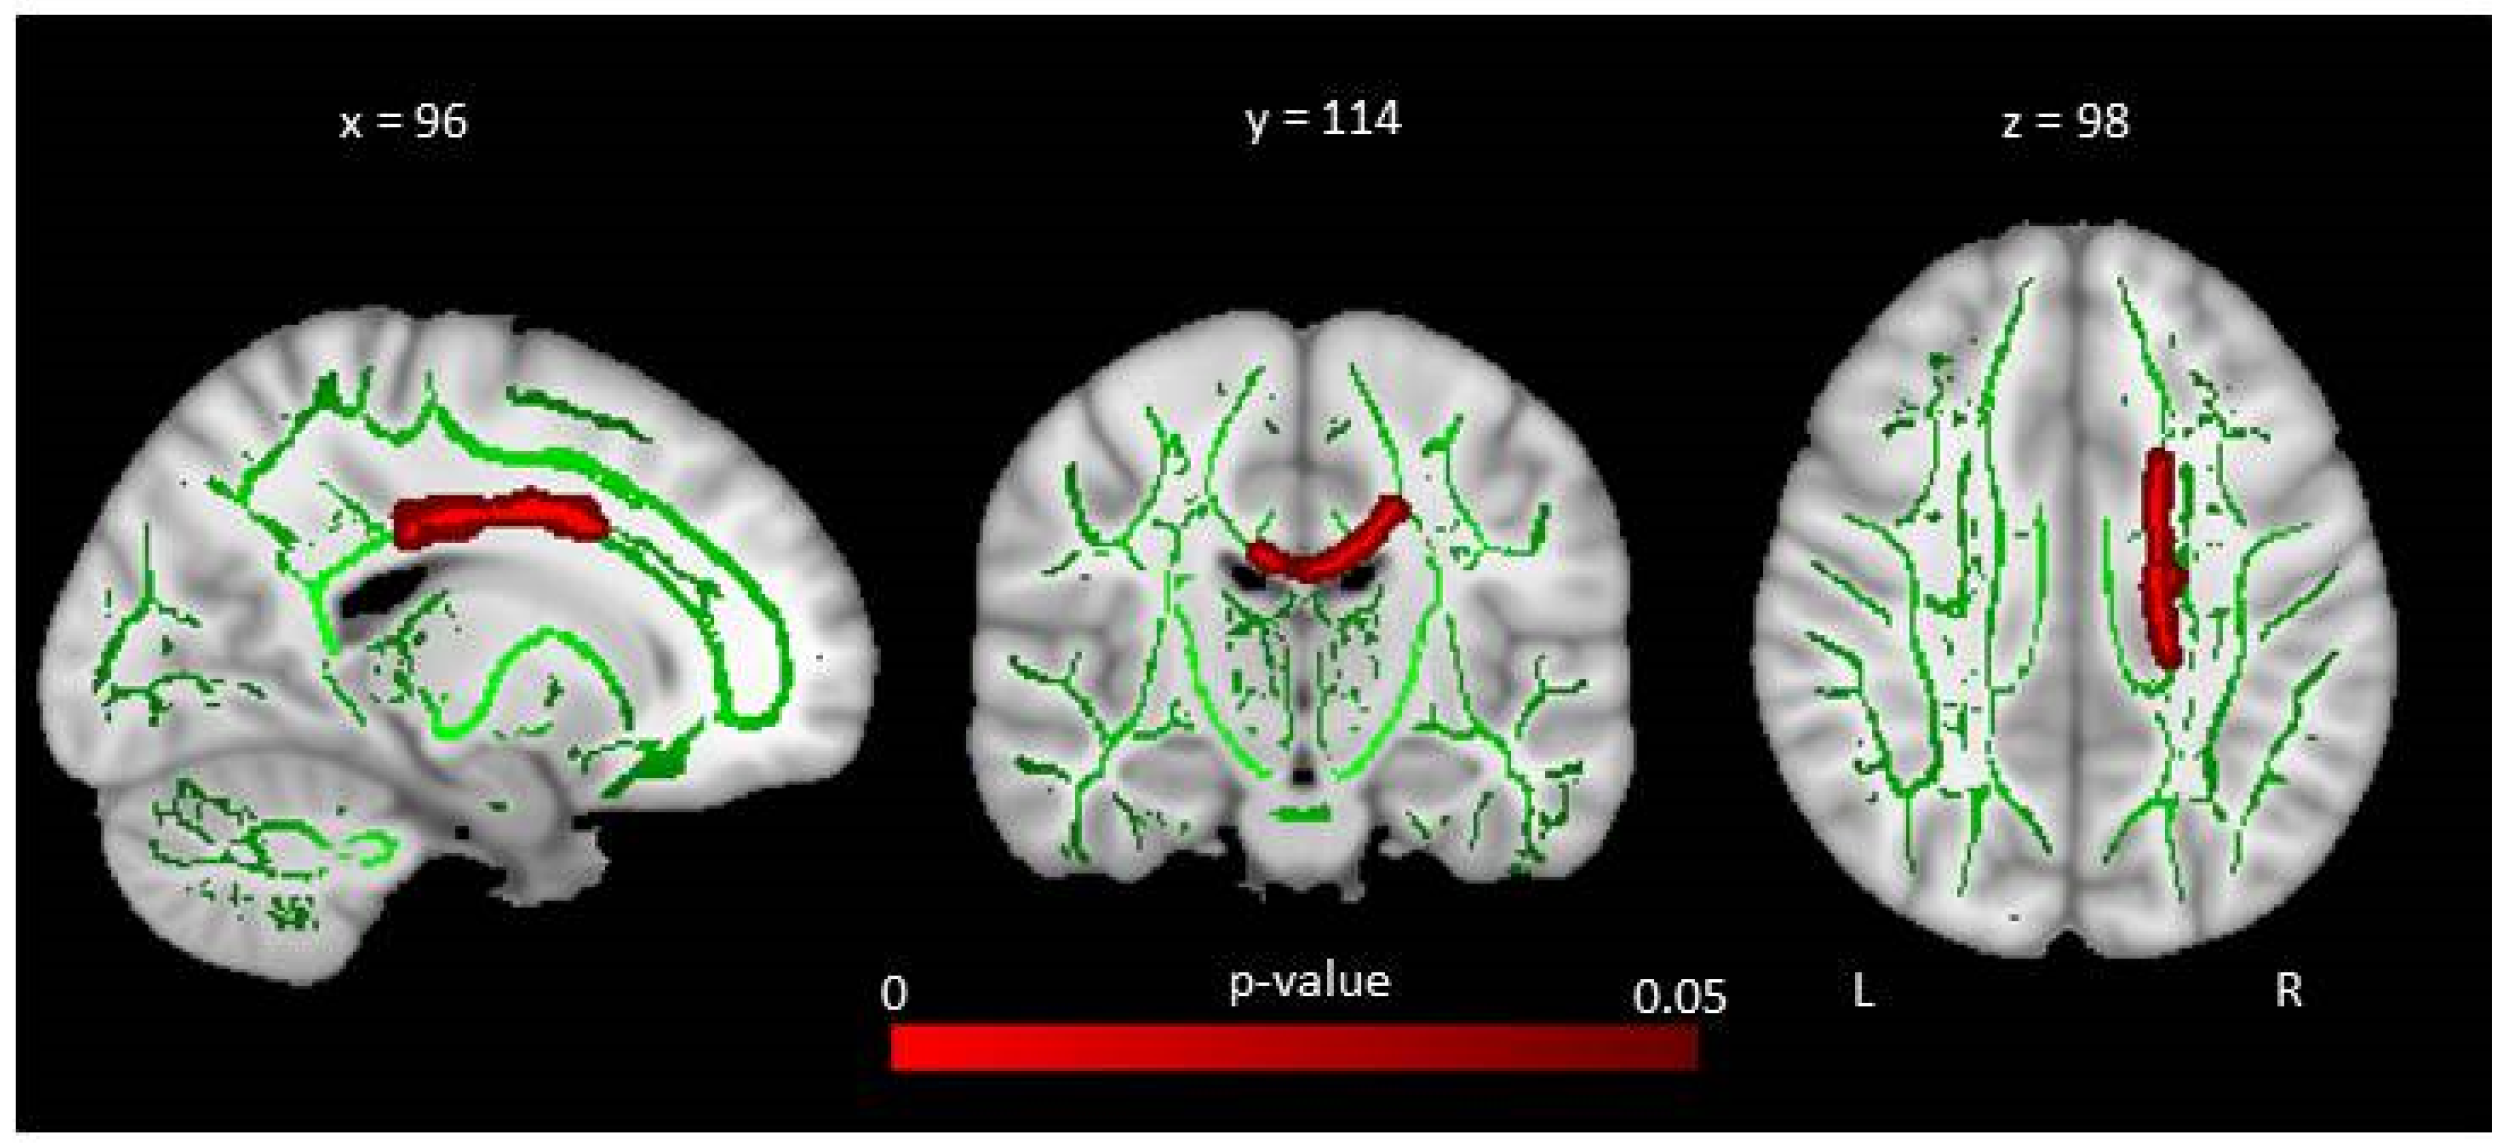

The study of resting brain function provides information on the level of activity of the different brain regions as a “baseline”, outside task performance. Using arterial spin labelling MRI (ASL-MRI), cerebral blood flow (CBF) can be measured at the cerebral level using intrinsic physiological contrast by labelling water protons from cervical arteries and measuring them once they are at the cerebral level [49]. In a recent study, we compared arterial spin labelling images between patients with cystinosis and healthy controls, using a whole-brain approach [17]. We did not find any significant differences in resting cerebral blood flow values between groups. However, in cystinosis patients, the results showed a significant negative correlation between the cystine blood level and resting cerebral blood flow in the right superior frontal gyrus (Figure 4). Indeed, patients with higher levels of cystine were those presenting with lower resting cerebral blood flow values in the superior frontal cortex, which reinforces the link between cystinosis disease and abnormalities within frontal brain regions. Importantly, the superior frontal cortex is associated with executive functions, and the described abnormalities could underline the neurocognitive deficits described in cystinosis patients, such as memory impairments or further cognitive impairments.

Figure 4.

Advanced neuroimaging techniques can help in understanding the impact of cystinosis on the brain’s anatomo-function and its link with neurocognitive impairments. For instance, here, we illustrate the results of Scheme 10 (y = 50 z = 40), a brain region strongly implicated in cognitive functions: the higher the cystine levels, the lower the resting CBF in this area, which is associated with cognitive functions. Maximum intensity projections of T statistics clusters that are significantly correlated with individual cystine blood level are superimposed on a 3D volume rendering on grey matter in the MNI space.